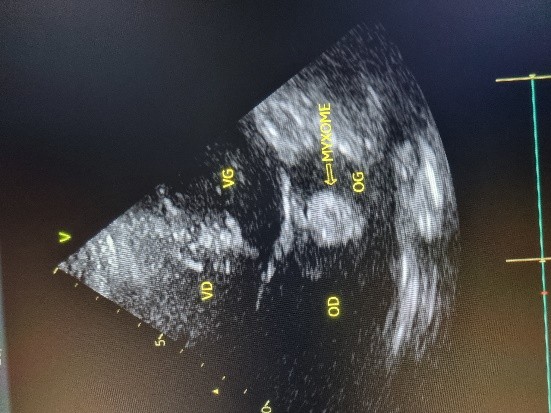

Figure 3 (a et b) : Echocardiographie transthoracique en mode bi dimensionnel montrant le myxome de l’oreillette gauche appendu au septum inter atrial vu en mode 4 cavités (a) et 2 cavités (b) chez un patient de 54 ans (Cas clinique n°2). VG= ventricule gauche; OG= oreillette gauche; OD= oreillette droite ; VD= ventricule droit.

(a)

(b)